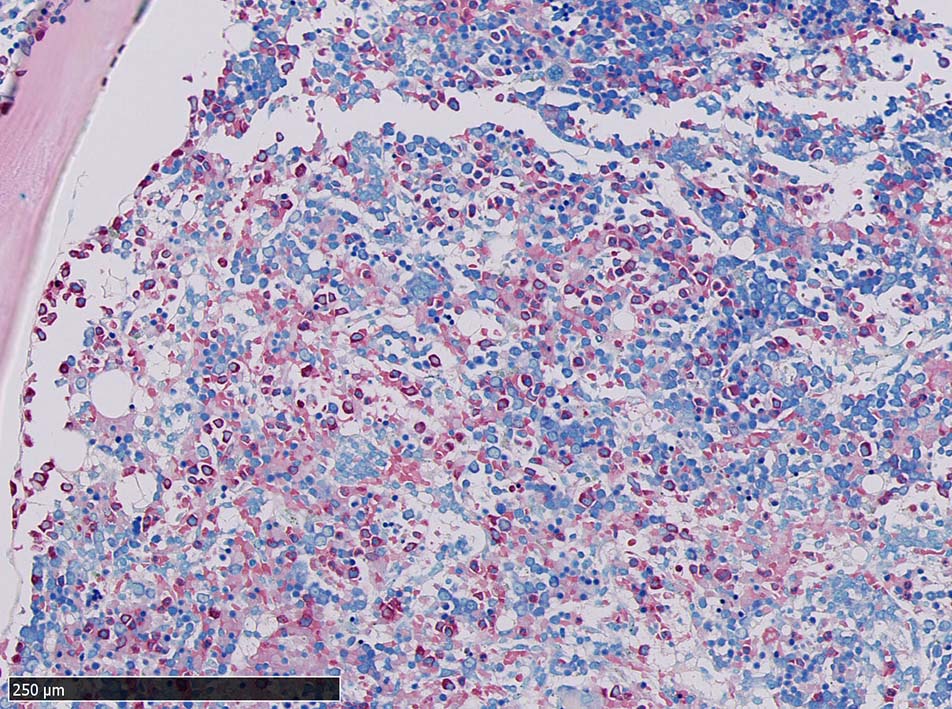

骨髄浸潤所見

同じ患者さんの骨髄所見です. (サムネイルのクリックで大きな画像が見られます.)

骨髄への腫瘍細胞浸潤はintertrabecular patternで, 腫瘍細胞は小集簇巣を形成して散在性に認められた. HE, ASD-Giemsaのみでの浸潤, 増殖の確定はなかなか難しいようです.

ASD-GiemsaではASDに染まらない(陰性の)あやしい細胞塊があるように見える. 細胞小塊はCD3陽性.

骨髄クロットでは, 十分量が採取されているにもかかわらず, CD3陽性細胞は微小な集簇巣が2個ほど認められるのみであとは散在している.

免疫染色でCD3陽性となる細胞集塊のASD-Giemsa像. 肝類洞内浸潤細胞に比較して核, 細胞が紡錘形の傾向を示している.